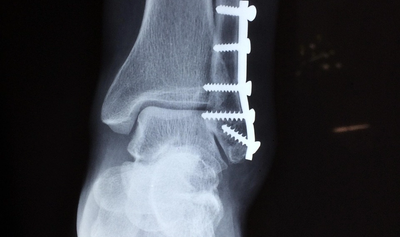

Procedura presupune fracturarea femururilor, introducerea unor tije metalice și montarea de fixatori externi, care sunt ajustați zilnic pentru a forța creșterea osului. Recuperarea este lungă, dureroasă și adesea umilitoare: luni întregi pacienții trăiesc cu dispozitive atașate de picioare, sub un regim strict de fizioterapie, masaje, medicamente pentru durere și anticoagulante. Este și cazul unui pacient care a relatat 'ororile' prin care a trecut pentru doar câțiva centimetri în plus, potrivit The Guardian.

Operația nu este lipsită de riscuri. Printre complicațiile posibile se numără formarea cheagurilor de sânge, infecțiile, durerile cronice sau așa-numitul „sindrom al balerinei” – o afecțiune în care tendonul lui Ahile nu se adaptează și pacientul ajunge să meargă permanent pe vârfuri. În 2023, un pacient din Arabia Saudită a murit la 16 zile după intervenție, în urma unei tromboze. Clinica a declarat că nu s-au identificat erori medicale, potrivit sursei citate.